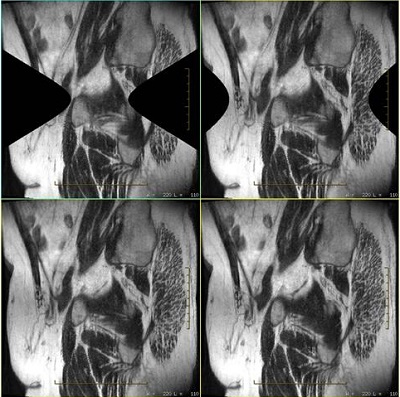

Figure 2. Sagittal T2 Cube pelvis images

The example below shows images at the edge of the volume acquired with 3D Geometry Correction turned On. Portions of the image display as blank due to the through-plane correction, which is expected behavior. The pattern and amount of the image which is blank can vary depending on the position of the acquired volume